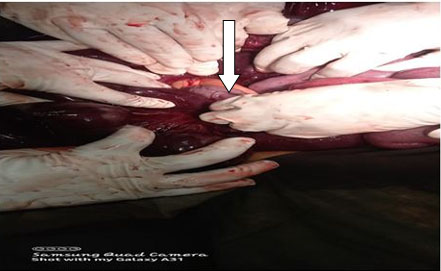

There was abundant blood in the gastric fundus (Figure 1); however, no discernible active bleeding was found in the esophagus (Figure 2), stomach, or first two parts of the duodenum. A medium-sized hiatus hernia measuring about 4 cm was noted (Figure 1) and on closer inspect a Cameron lesion was identified with overlying blood clot (Figure 3) in the hiatus hernia. Hemospray® endoscopic sealant (Cook Medical) was sprayed over the clot (Figure 4).